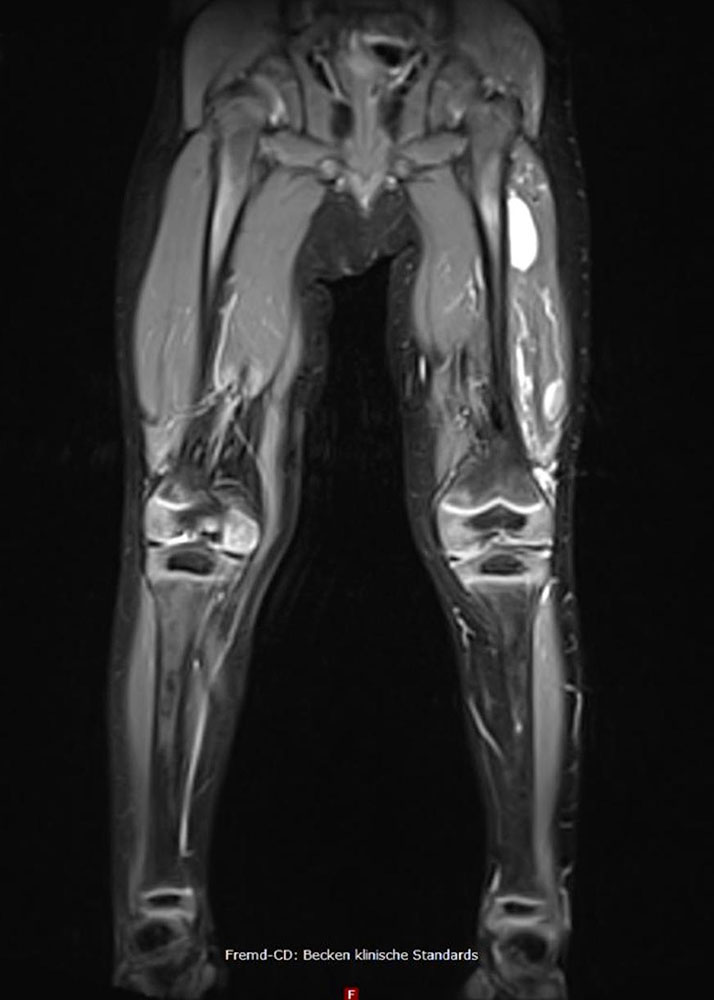

Depending on the volume of the venous malformation, blood congestion occurs because of hydrostatic pressure. Depending on posture, this congestion worsens and triggers troublesome tightness. Since the accumulated blood is also warmer than the surrounding soft tissue, it acts like an “internal radiator”, increasing the discomfort. The location of the malformation also influences the degree of congestion and thus the pain, which is described as dull. Venous malformations of comparable volume are more painful in the legs than in the arms or face because of the higher hydrostatic pressure. Within the subcutis, venous malformations can expand over time and thus are increasingly filled with more blood. Within the muscles, however, the muscle fascia and muscle tone limit the extent of congestion. Larger malformations, which are mainly formed subfascially in the muscles, cause comparatively little pain, especially if they are surrounded by properly developed muscles. On the other hand, smaller subfascial VMs near the knee or on the sole of the foot can cause severe, load-dependent pain.